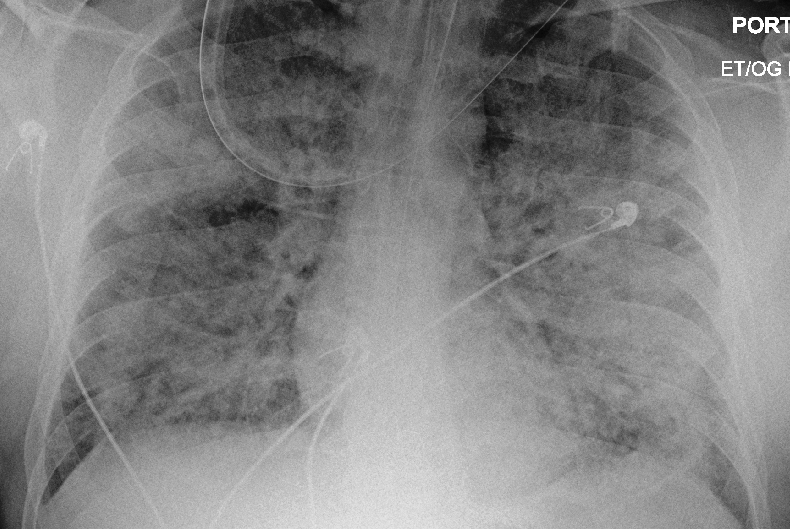

Young people could get seriously ill too. They could suffocate to death when their lungs fill with fluid from acute respiratory disease symptom, and they can’t breathe any more.   Their minds would grow dim as their lives ebbed away. We could spend the rest of our lives grieving a loved one. Just because we weren’t that concerned how we would know if we had COVID-19.

Preview Image: Person with Severe ARDS